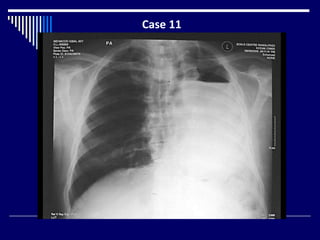

Case 11

Findings

CXR

Opaque left hemi thorax with air fluid level (2)

Ipsilateral mediastinal shift (2)

Overinflated right lung (2)

Dx =Left pneumonectomy (4)